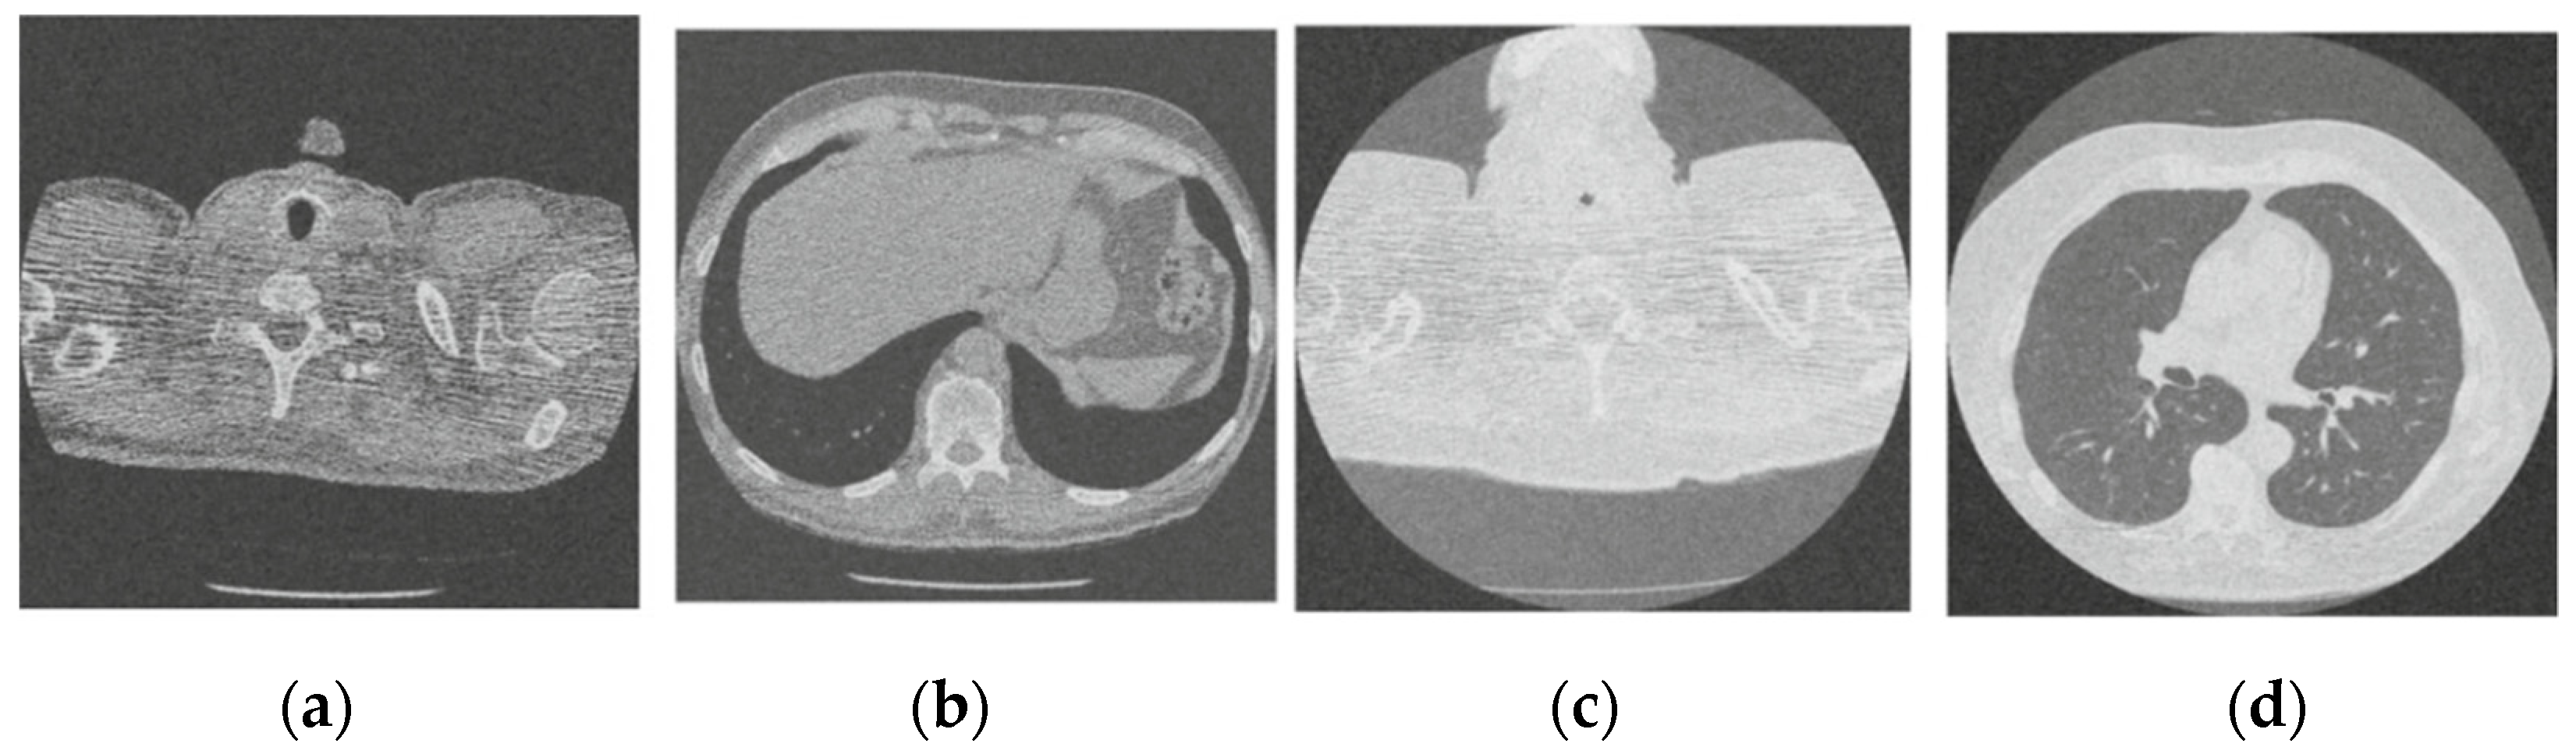

Figure 3 shows the corruption of a CT image after the addition of 20% Gaussian noise. The degradation in image quality is visible to the naked eye without aid when compared to the original CT image. Figure 4, Figure 5, Figure 6, Figure 7, Figure 8, Figure 9, Figure 10 and Figure 11 show the denoised CT images, corresponding to CT images in Figure 3 and generated from various denoising models. The results show a discernible reduction in both the gaussian noise introduced, as well as the noise present in the original CT image whilst safeguarding the finer details present in it.

Figure 3.

Noisy CT image data set after inserting 20% noise); (a) Noisy CT1 image; (b) Noisy CT2 image; (c) Noisy CT3 image; (d) Noisy CT4 image.